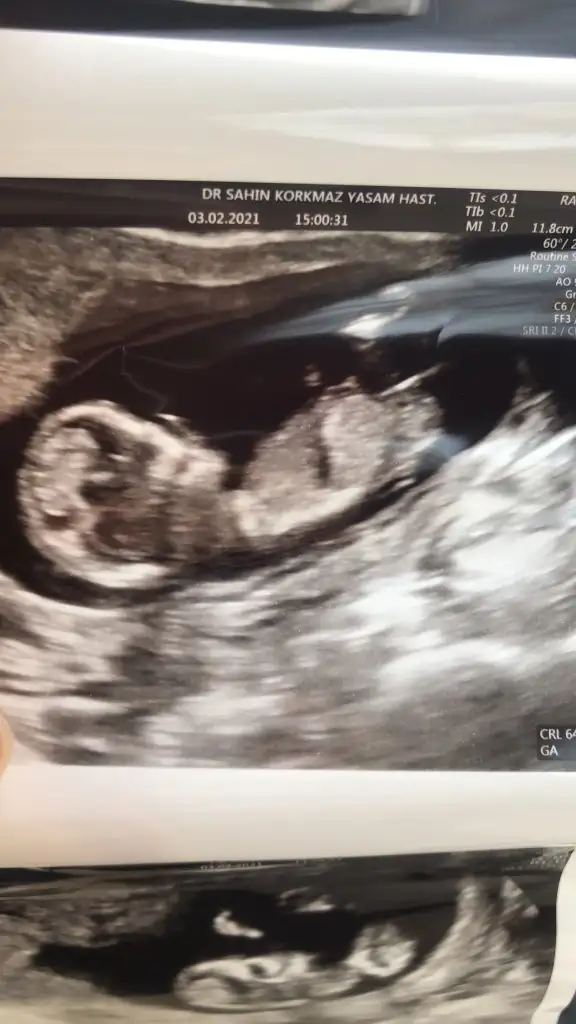

11+2 de ki karından ultrason görüntümüz bir şeyler gören varsa yazabilir mi? 😊

• WhatsApp Image 2021-02-03 at 11.18.19.webp

WhatsApp Image 2021-02-03 at 11.18.19.webp

48 KB · Görüntüleme: 226